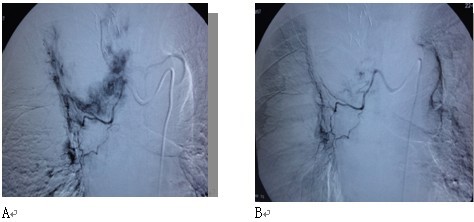

在冷冻治疗前后,作血管介入区域性化疗,适用于肿瘤较大,伴多发性转移者。我们采用特殊技术,将远比一般化疗剂量为少的药物配置成≤100nm的微颗粒,通过微导管输入肿瘤血管。微颗粒通过泄漏的肿瘤血管大量聚集于瘤灶内,以致肿瘤内化疗药物浓度高,瘤内微血管被栓塞,但由于微颗粒不能透过正常血管,因此不会导致严重副作用。我们将此种血管介入成为“肿瘤微血管介入”(cancer microvascular intervention,CMI)。实验显示,此法中应用的化疗药仅为常规化疗的1/10,但肿瘤内药物集聚量是常规化疗的40-50倍。在冷冻和/或碘粒子植入后仍残留病变者,给予CMI可使病变内血管迅速消失,从而强化消融效果(图6 )。

图6 微血管介入与冷冻、碘粒子植入的相辅相成作用。 图示左肺癌,冷冻加125碘粒子植入一周,血管造影在肿瘤周边区仍有肿瘤血管染色(A),通过微导管注入微颗粒化疗药(CMI),原先血管染色大部消失